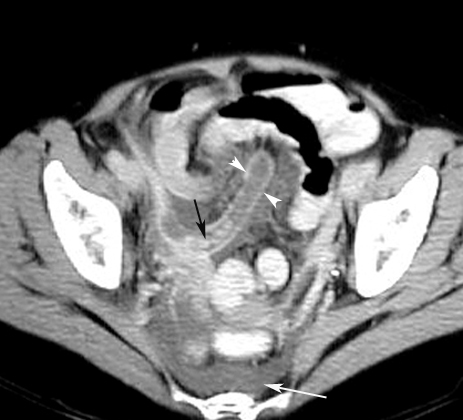

CT: Highly accurate

Signs: